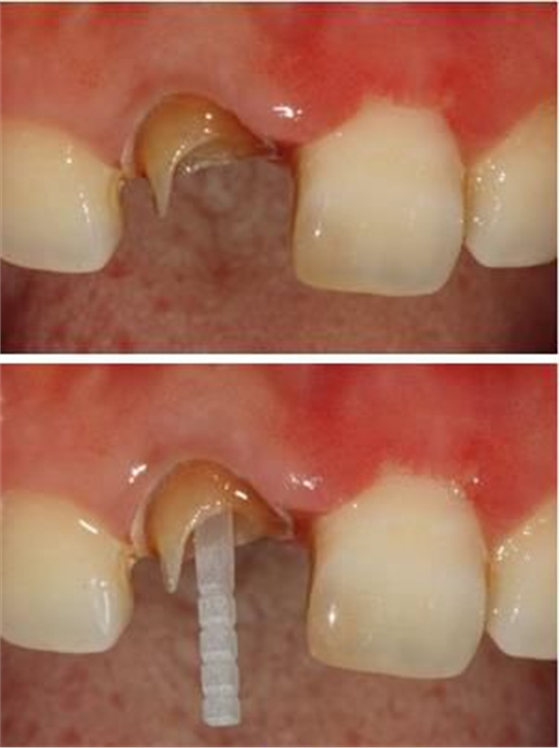

在操作的過程中要注意無菌操作,保證纖維樁的無菌狀態(tài)。推薦將樹脂核堆好之后再截斷纖維樁,而不是截斷后再粘接。如下圖: